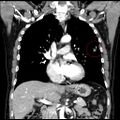

5. 2023/10/20 조영제 CT 촬영

2. 대표사진 - 사진 속 빨강 원이 문제의 결절

3. 사진을 동영상으로 변환. 노랑 원이 문제의 결절

6. 2023/10/24 호흡기내과 김성경의사와 상담

1. 조영제 투입된 CT 사진을 볼 때 수술해야겠다.